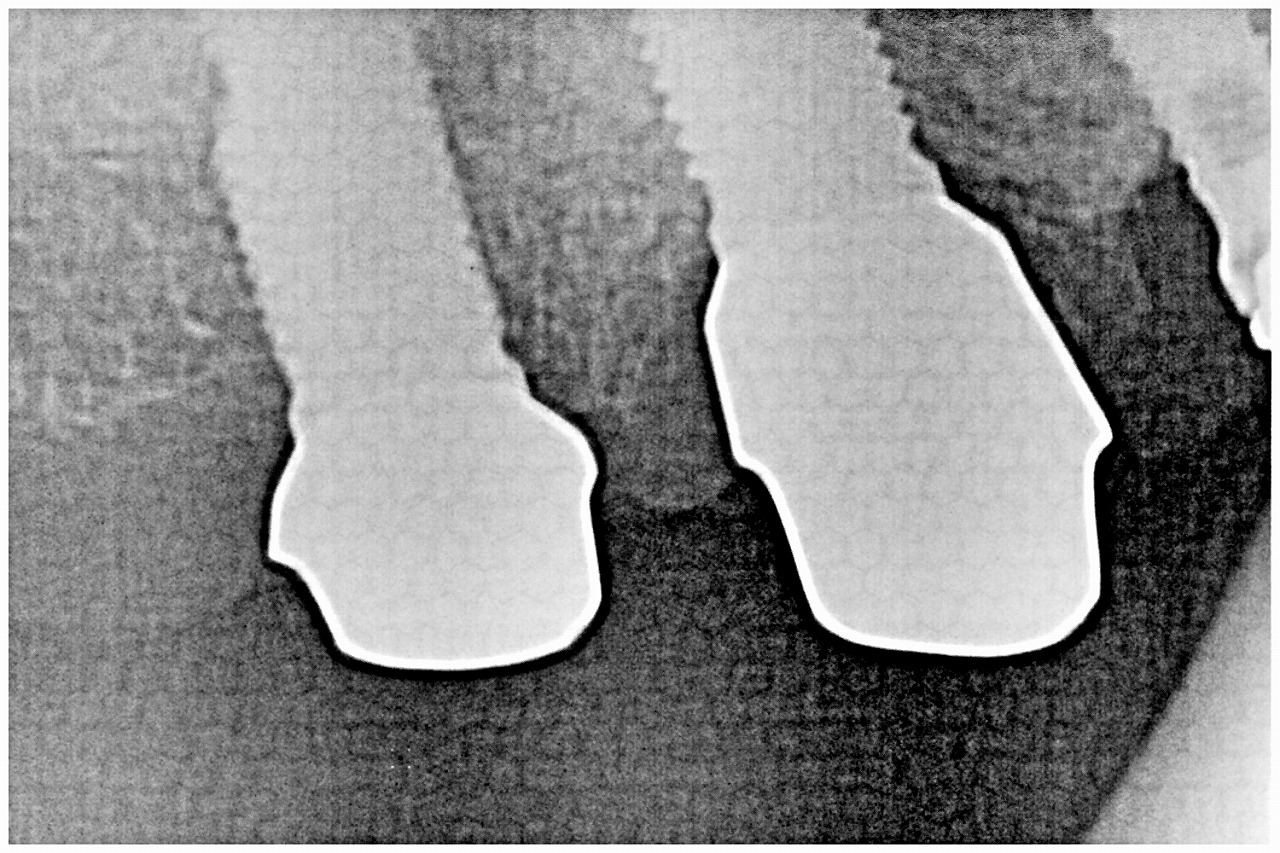

7番部のインプラント埋入になります

5mmの13mmというインプラントを埋入しています

6番部のインプラントを埋入になります